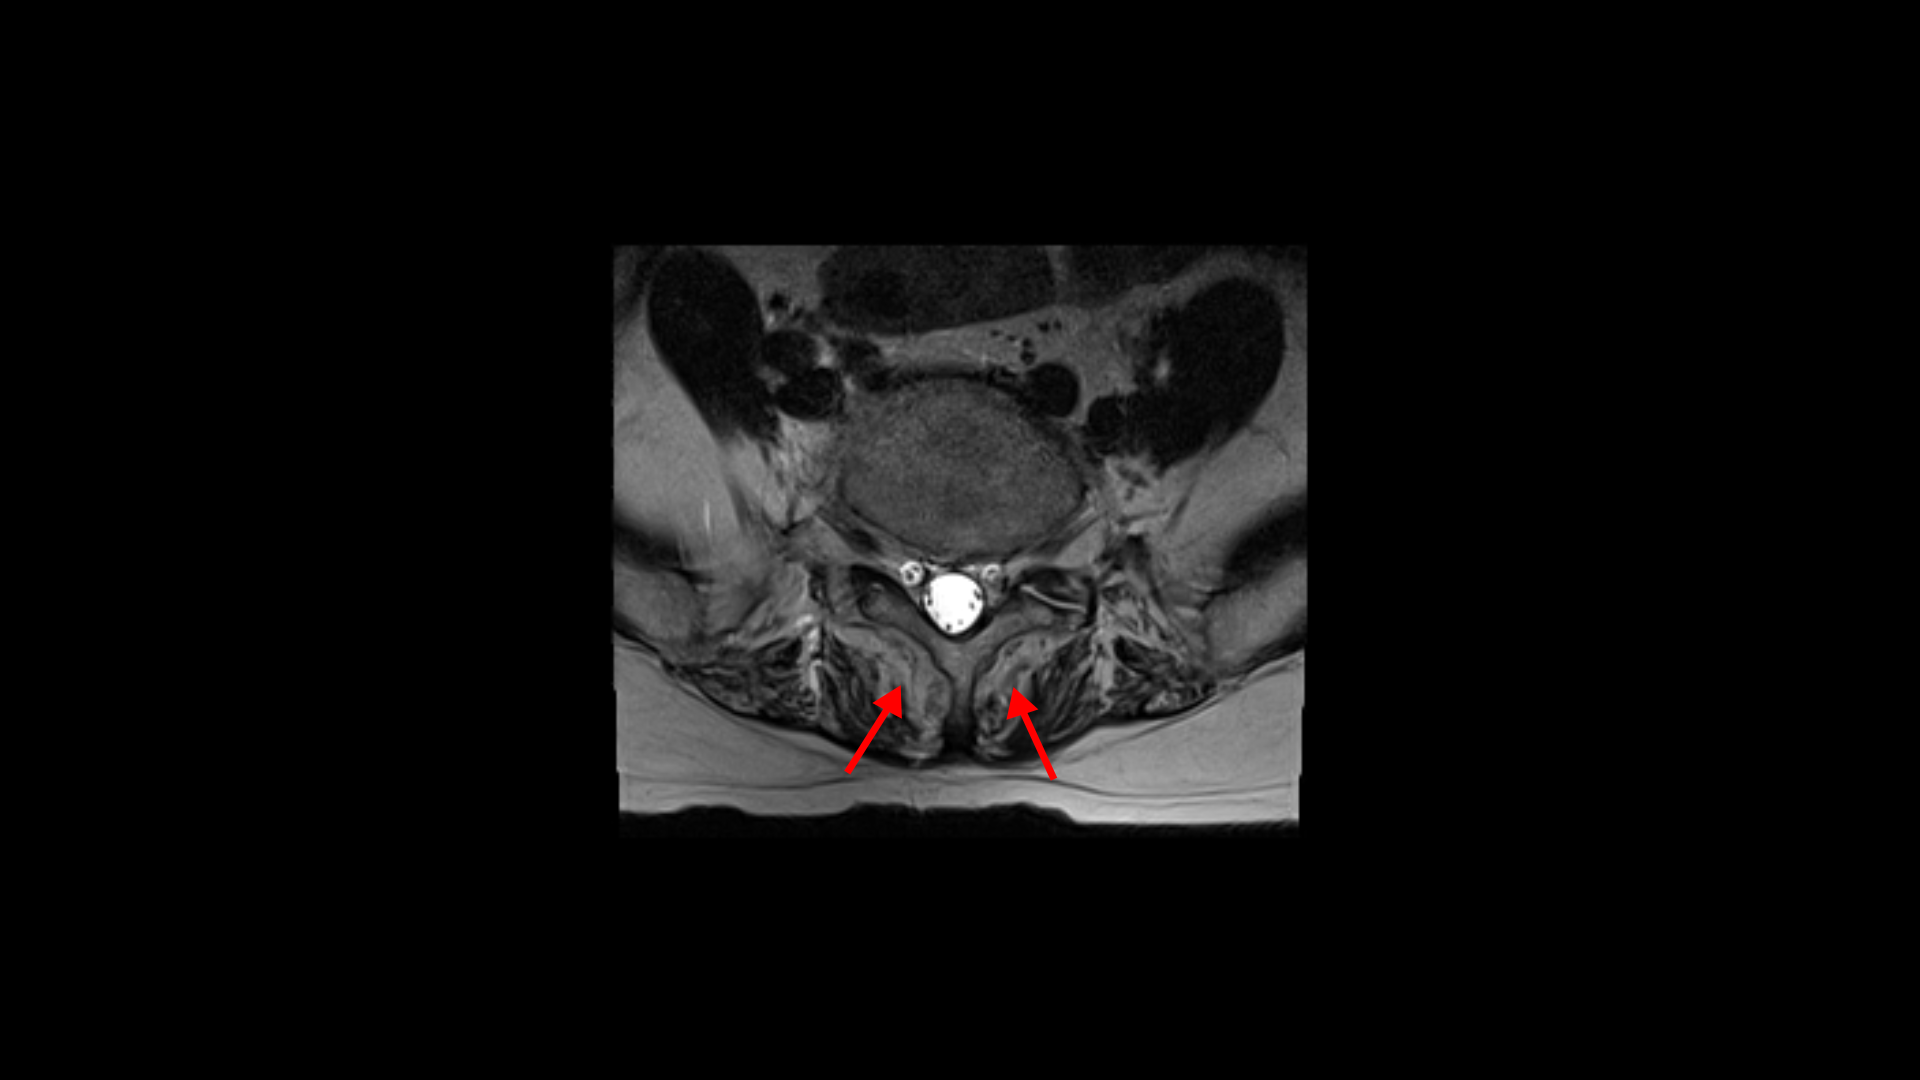

이 환자분의 일어서면 허리가 구부러지고 다리가 아파 걷기 어려운 이유는 근감소증 때문입니다. 특히 근육 중에서도 MRI에서 보면 허리 뒷부분에서 허리를 펴주는 근육인 기립근이 보시다시피 하얗게 지방으로 변해있습니다.

이분하고 증상이 비슷한 다른 근감소증 환자분의 기립근도 마찬가지입니다.

이분도 근감소증 치료후기가 있으니까 꼭 보세요. 이렇게 기립근이 지방으로 심하게 변해버린 분들은 허리를 펴주고 세워주는 근육의 기능이 떨어지니까 일어서서 걸으려고 하면 허리가 그냥 앞으로 구부러져 버리는 것입니다.